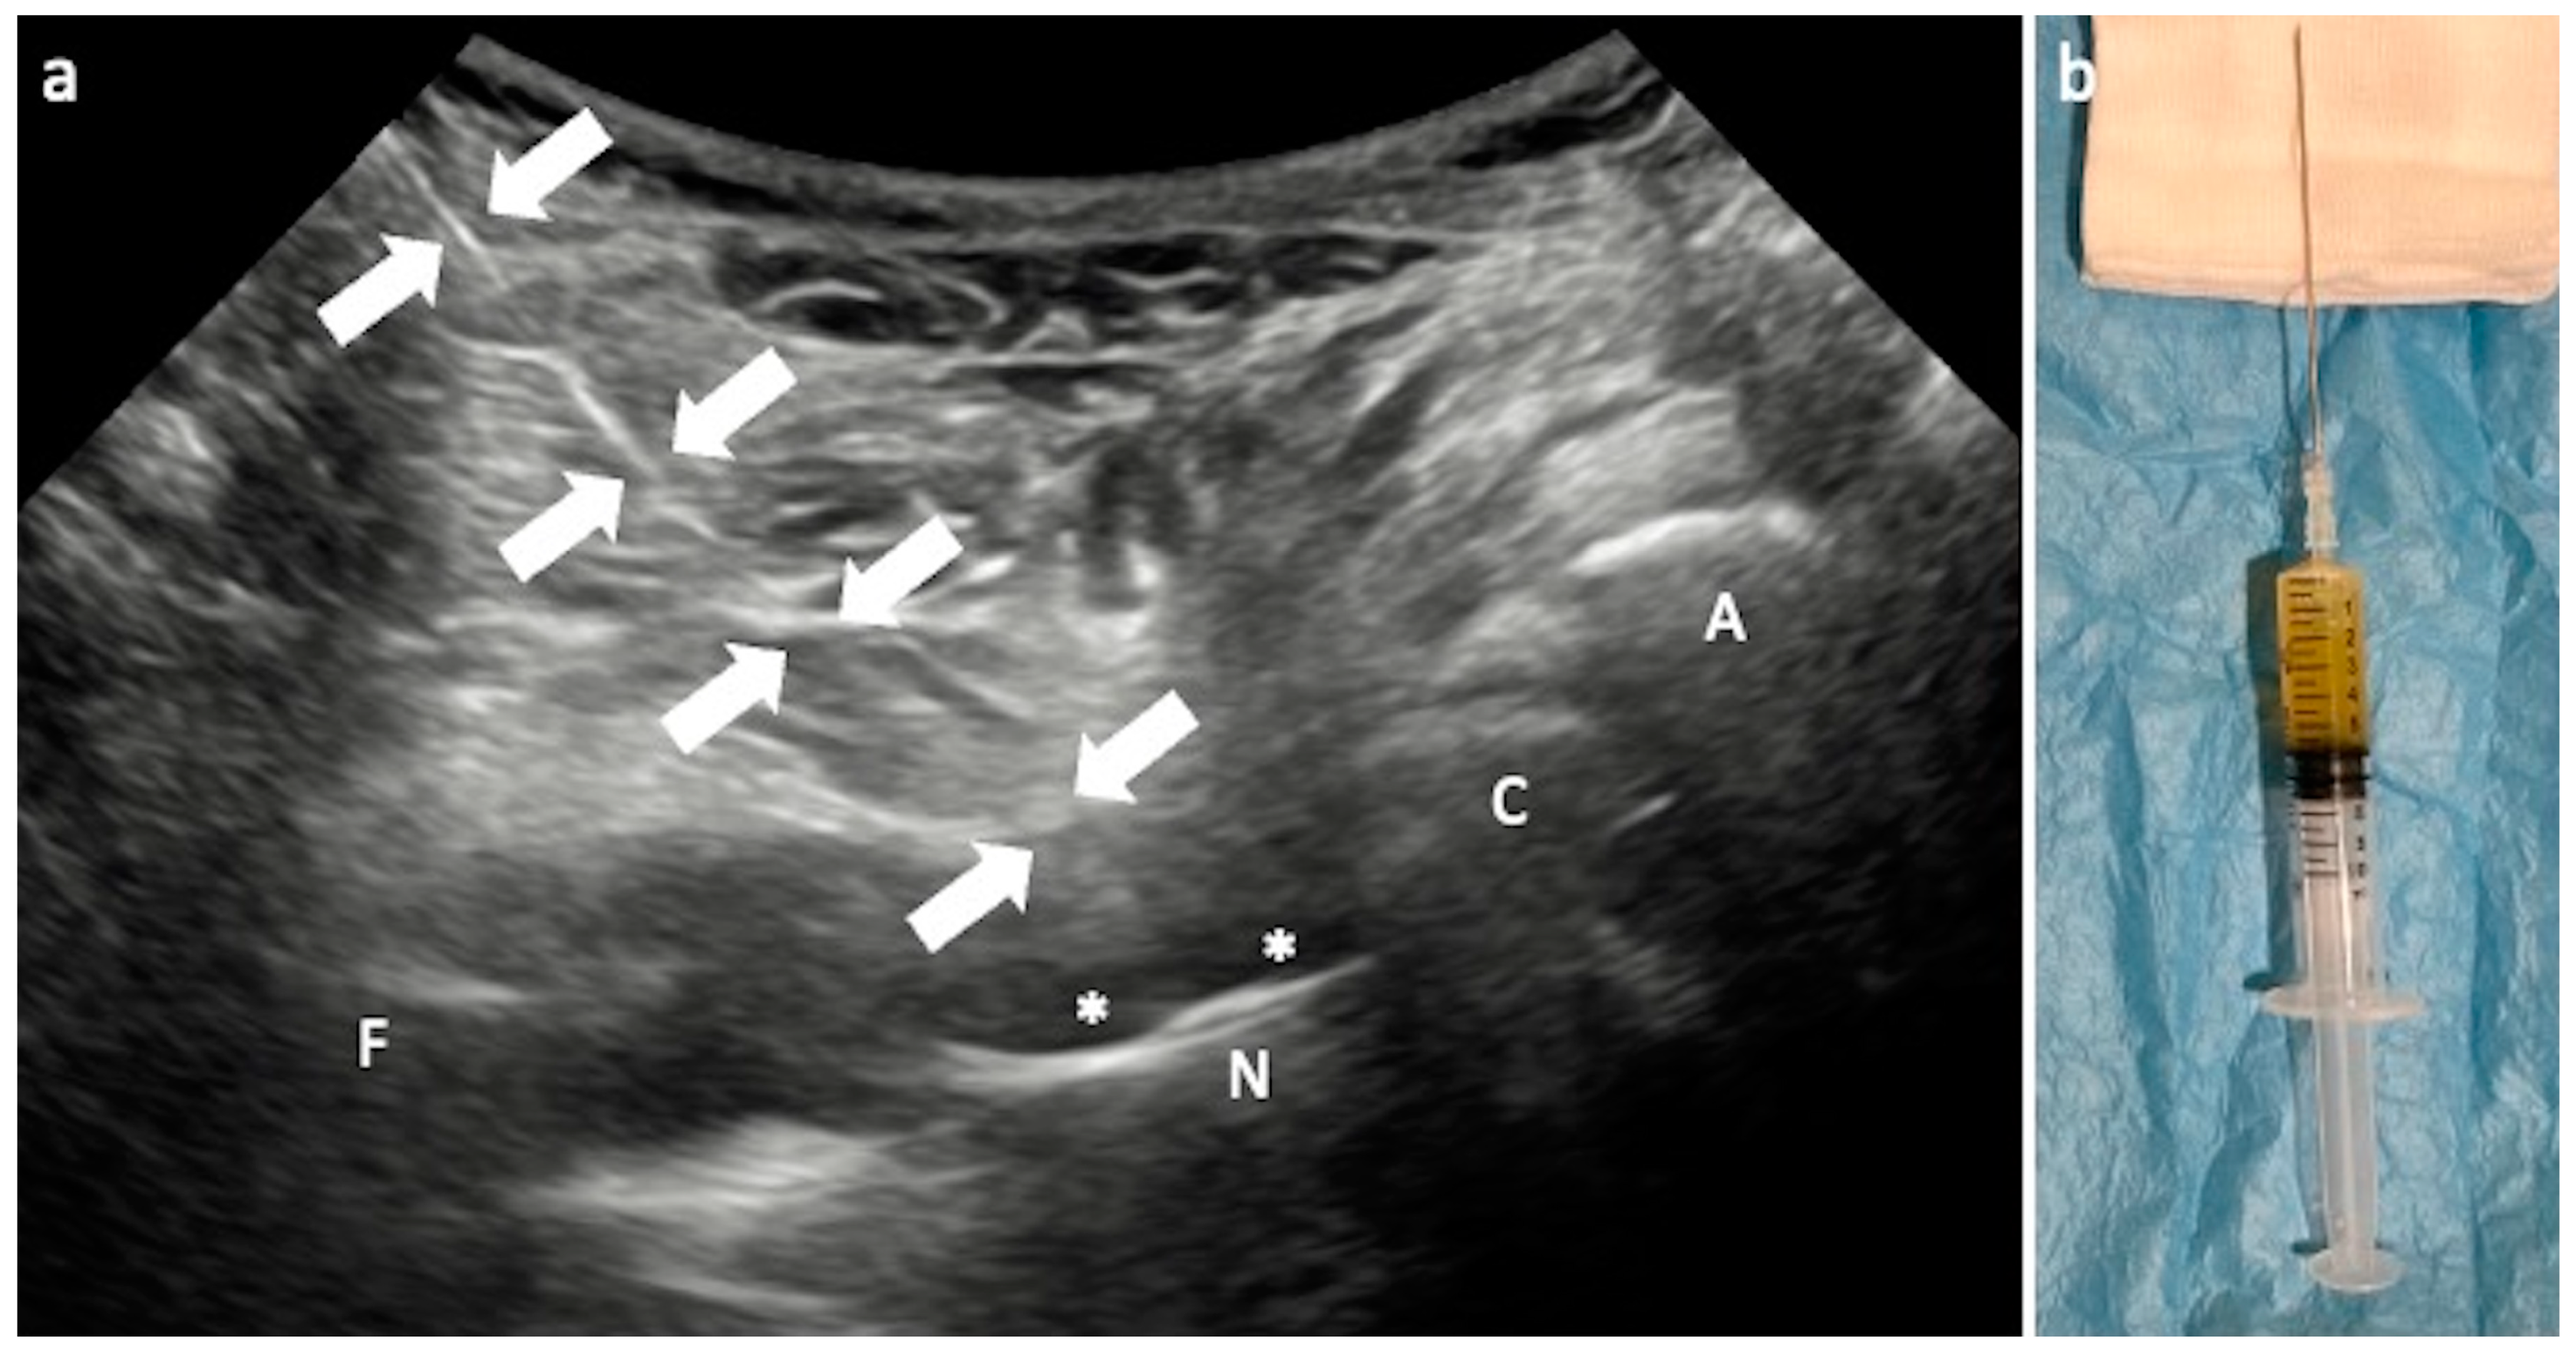

3.1. Arthrocentesis and Periprosthetic Biopsy

Technical Considerations

- Sconfienza, L.M.; Albano, D.; Messina, C.; D’Apolito, R.; De Vecchi, E.; Zagra, L. Ultrasound-Guided Periprosthetic Biopsy in Failed Total Hip Arthroplasty: A Novel Approach to Test Infection in Patients With Dry Joints. J. Arthroplast. 2021, 36, 2962–2967. [Google Scholar] [CrossRef] [PubMed]